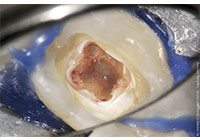

齲齒由口腔中多種因素復合作用所導致的牙齒硬組織進行性病損,表現為無機質脫礦和有機質分解,隨病程發展而從色澤改變到形成實質性病損的演變過程。齲齒是細菌性疾病,因此它可以繼發牙髓炎和根尖周炎,甚至能引起牙槽骨和頜骨炎癥。(圖01~04)

圖3

圖4